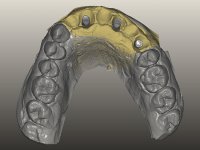

O paciente foi observado conjuntamente e a dúvida que surgiu de imediato foi se seria possível com a regeneração óssea a efectuar poder ser reabilitada naturalmente a zona das papilas interdentárias. Nesse sentido foi feito um enceramento de diagnóstico que contemplaria as duas hipóteses, utilizando ou não a cerâmica gengival. A confecção desse enceramento foi fundamental para expor ao paciente a dificuldade da reabilitação. O wax-up deu origem a um mock-up que foi aprovado pelo paciente e que simultaneamente serviu de guia imagiológica. O caso foi planificado cirurgicamente e realizada uma guia cirúrgica com que foram colocados os implantes. Após 10 semanas foi feita a 1ª impressão para confecção da ponte provisória. Foram criados os primeiros perfis de emergência na gengiva artificial e foi digitalizado o modelo. Por processo de CAD-CAM foi confeccionada uma ponte provisória aparafusada baseada no enceramento de diagnóstico. A ponte trabalhou durante 8 semanas os tecidos moles que foram fielmente copiados numa impressão com técnica de moldeira aberta. Os transferes foram individualizados com resina composta para copiarem fielmente os perfis de emergência criados pela ponte provisória. Confeccionado o modelo de trabalho definitivo, foi realizada uma infra-estrutura em zircónio seguindo a orientação do enceramento de diagnóstico. O assentamento da infra-estrutura foi testado em boca e simultaneamente foi novamente impressionados os tecidos moles com um silicone fluido. Nessa consulta foi feito o levantamento da cor. Os dentes 13 e 23 apresentavam uma saturação anormalmente forte que resolvemos não valorizar, optando por privilegiar a relação com o sector antero-inferior. Foi realizada uma nova gengiva artificial com a impressão que acompanhou a impressão de arrasto com a infra-estrutura. Após a colocação da cerâmica na infra-estrutura foram coladas as meso-estruturas. O trabalho final foi aparafusado lentamente permitindo a adaptação dos tecidos moles.